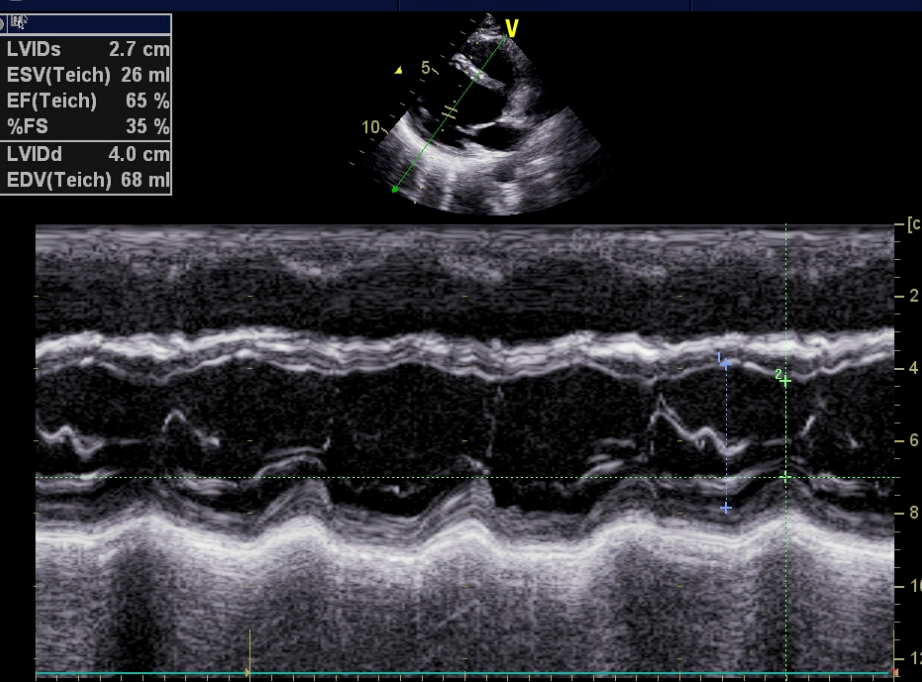

三、M型超声:也属辉度调制型,与A型不同的是,M型是辉度扫描,以运动曲线显示。

工作原理:为一维超声,是B型诊断仪的一种特型,采用辉度调制,在水平偏转板上加入一对慢扫描锯齿波,其横坐标表示时间,纵坐标表示距离。

彩超logiq怎么读B超、彩超“傻傻分不清楚”?其实区别就在这!_https://www.jmylbn.com_新闻资讯_第7张

应用范围:多用于心脏检查

(1)心脏的前后方向结构层次

(2)测量心腔前后径及厚度

(3)观察运动轨迹

(4)测量心动功能